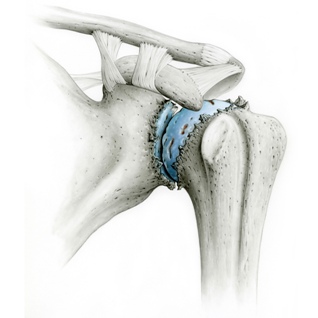

Unter Schultergelenksarthrose (Omarthrose) verstehen wir den Verschleiß des Schultergelenkes durch eine Verminderung und Zerstörung der Knorpelsubstanz. Im Extremfall reiben Oberarmkopf und Gelenkpfanne knöchern aufeinander, was zu einer stark schmerzenden Schulter mit Gelenkentzündung und Bewegungseinschränkung führt.

Oft ist die Ursache des Schultergelenkverschleißes eine kontinuierliche Abnutzung  des Gelenks über Jahre (primäre Arthrose), manchmal tritt diese Abnützung auch als Folge eines anderen Schulterschadens auf. Beispiele sind ein früherer Oberarmkopfbruch (Humeruskopffraktur), ein großer chronischer Rotatorenmanschettendefekt oder Gelenkrheumatismus (sekundäre Arthrose).